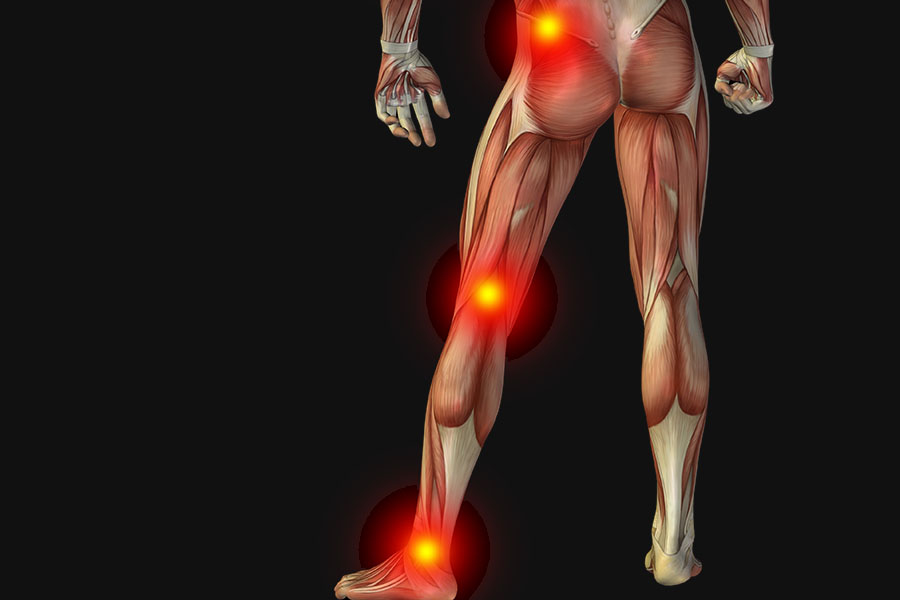

Sciatica is not the general back pain. Back pain is somehow a symptom of this acute disease but we cannot relate the origin of this disease with general backache. Sciatica occurs because of the pain in sciatic nerve which is located at one side of leg. To determine whether you are suffering or not, let’s have a look at sciatica symptoms.

Constant pain in one side of leg and in rare case, it’s in both legs

This shooting pain is basically anywhere along the sciatic nerve. The pain starts from lower back to the foot of one leg. It is usually severe in the leg as compared to the back.

Weakness or numbness while moving the leg

Weakness is another agony that is felt when you are suffering from sciatica. Your leg or foot falling asleep is a clear sign that your health is in trouble. You also might not be able to feel the pressure or sensation of hot or cold. This numbness is unlike the other short-lived ones because it is continuous and can obviously negatively affect the quality of life.

Lower back pain

You will feel a dull and aching pain in lower back. It is different than the burning, sharp or stinging one. This can achieve the severity in the form of muscle spasms, aches in pelvis and hips as well as limited mobility.